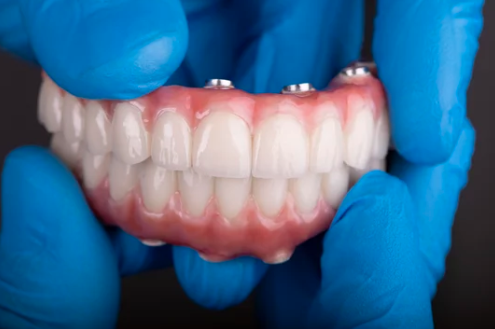

オールオン4とは、片顎につき4本のインプラントを埋入し、

その上にすべての歯が一体となった人工歯を固定する治療法です。

従来のように、歯1本につき1本のインプラントを入れる必要がなく、

身体的・経済的な負担を抑えながら、噛める歯を回復できる点が特徴です。